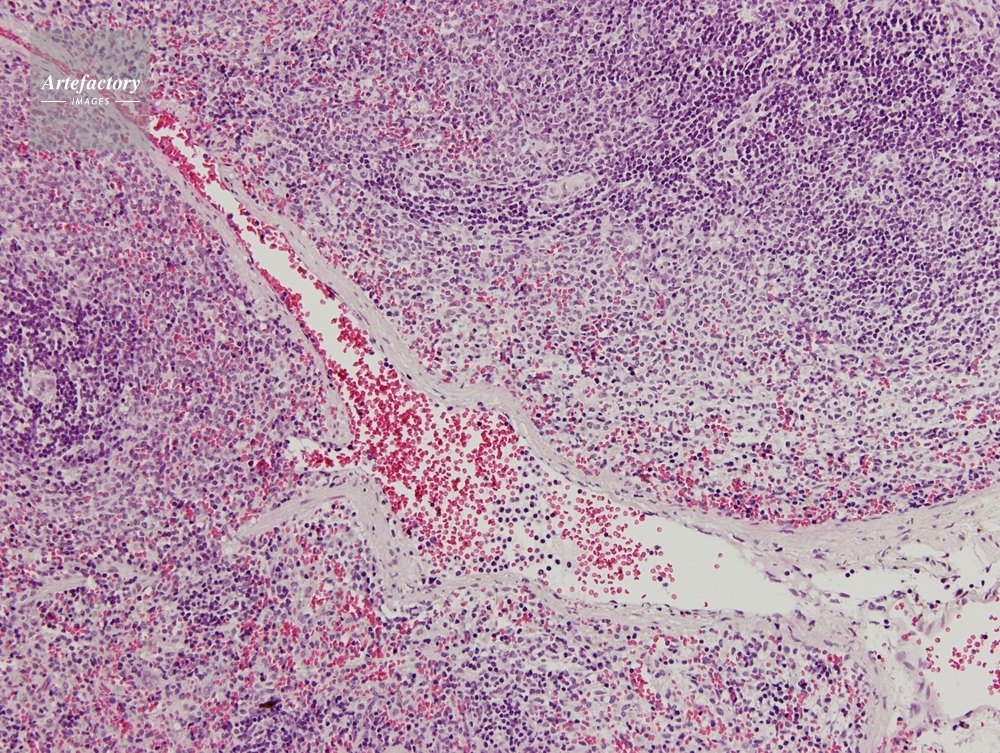

| 作品タイトル | マウス,脾臓 | モデルリリース | なし | |

| 作家 | OLYMPUS CORPORATION Technolab | プロパティリリース | なし | |

| ソース | ピクセル数 | 3455px × 2602px | ||

| 撮影地 | 印刷サイズ | 20.3cm × 15.3cm | ||

| 撮影年月日 | 2007/6/1 | データサイズ | 7.1MByte | |